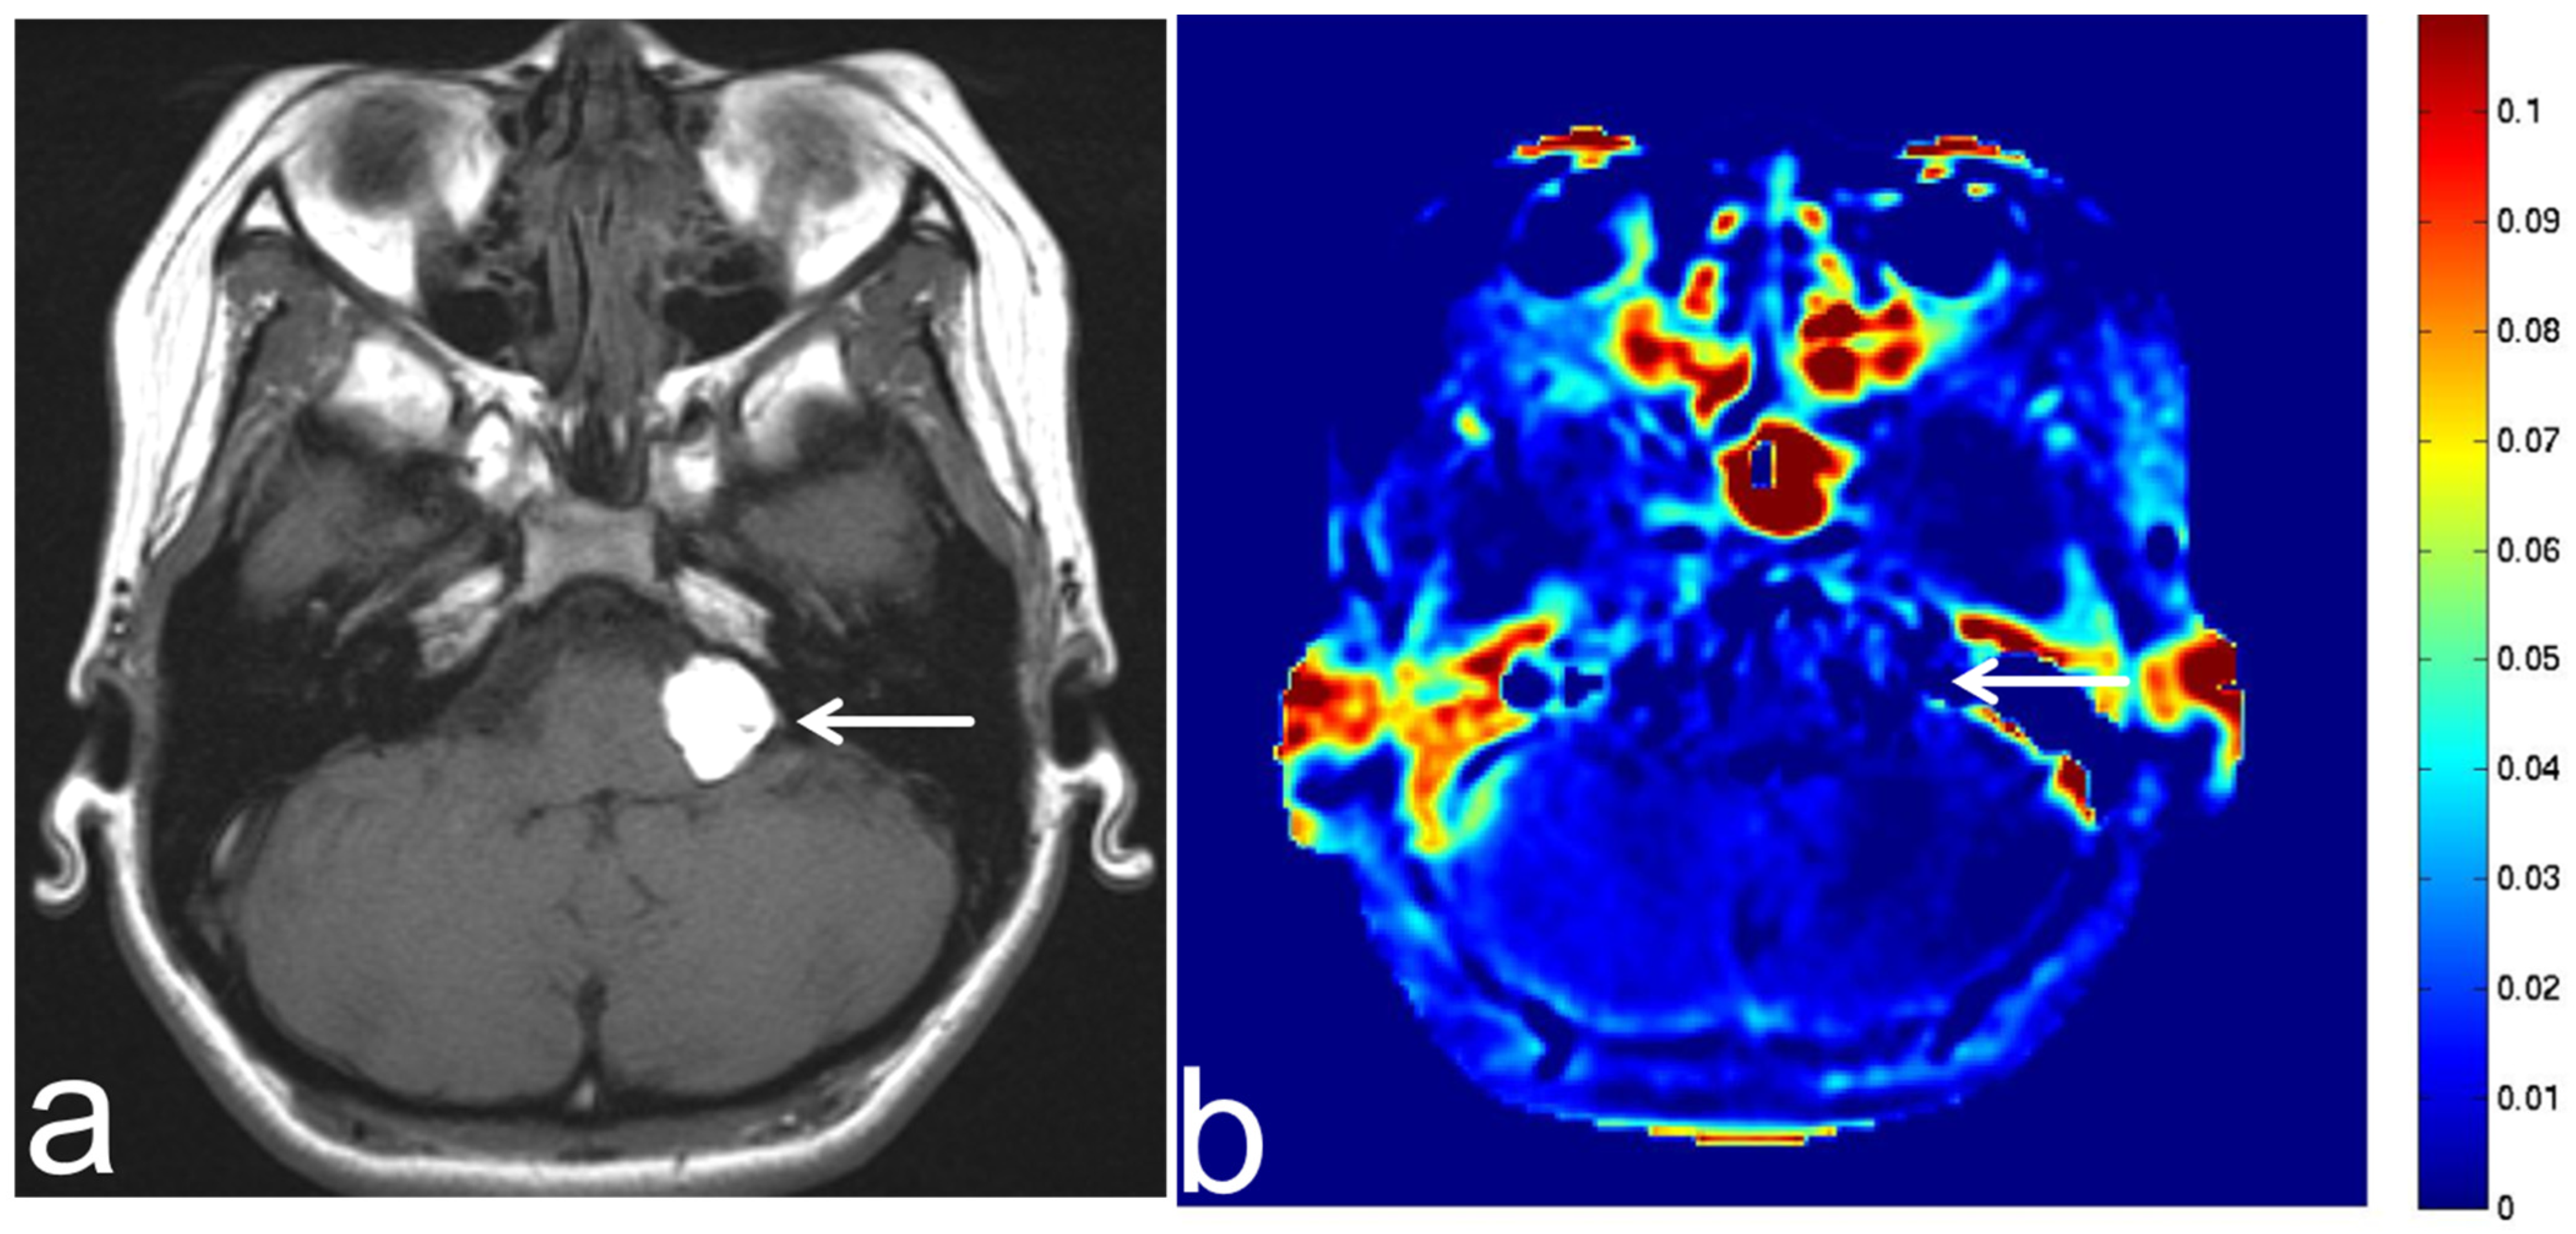

7.3. Schwannoma

7.4. Lipoma